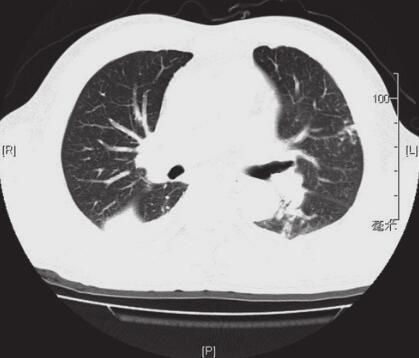

图2 2012年3月3日胸部CT

右肺中下叶及左舌段下叶见大片状模糊影,内部密度不均匀,见支气管充气征;两侧少量胸腔积液